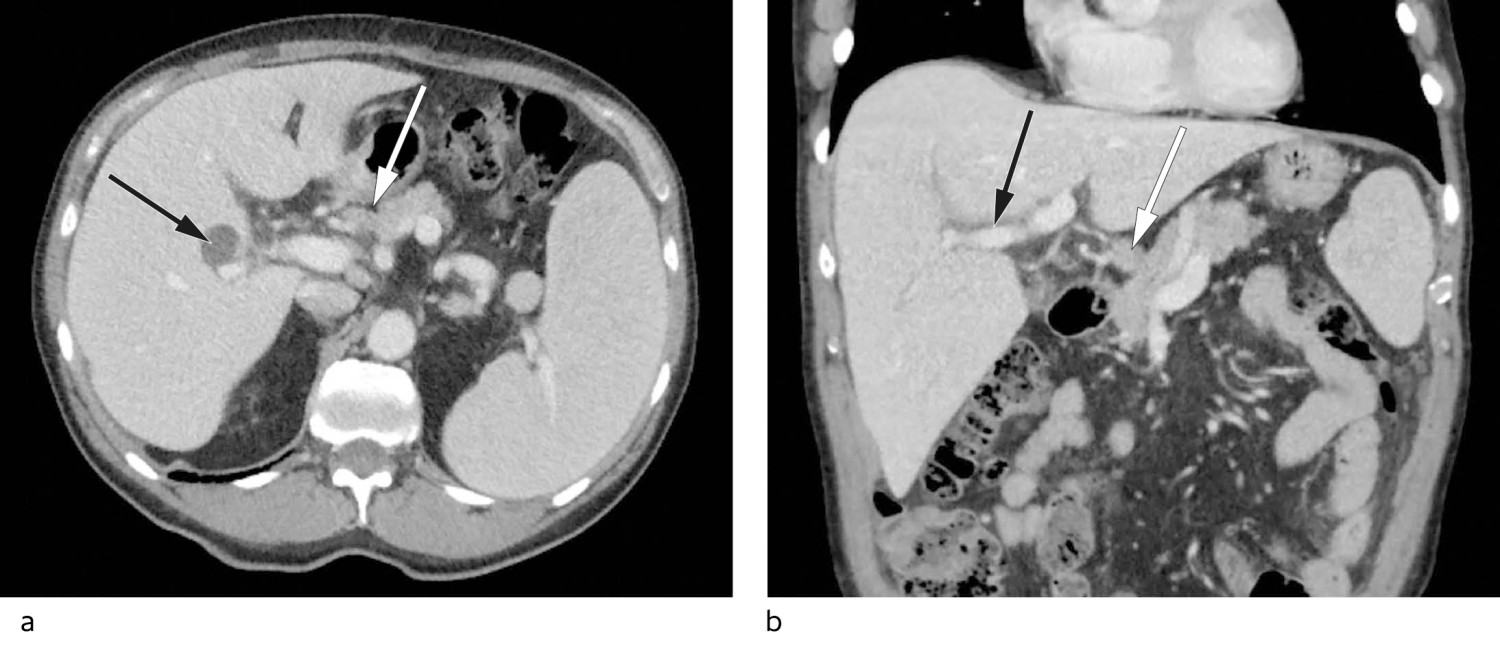

På bakgrunn av høy senkning, anemi, vekttap og påvirket allmenntilstand ble pasienten henvist til CT av hals, thorax, abdomen og bekken med intravenøs kontrast. Denne viste små mengder fri væske i bekkenet, splenomegali på 17 cm (lengste diameter), periportalt ødem og markerte lymfeknuter ved leverhilus, hvor den største var 11 mm i kortaksediameter (figur 1).

Periportalt ødem, som er væskeansamling rundt det portale kretsløpet, er et uspesifikt funn som kan gi mistanke om leverpatologi, men kan også ses ved ekstrahepatiske sykdommer (5). Splenomegali kan ses ved flere sykdomstilstander, eksempelvis portal hypertensjon sekundært til leversykdom, lymfom eller annen hematologisk malignitet. Isolert funn av lett markerte lymfeknuter ved leverhilus uten funn av forstørrede lymfeknuter andre steder gjorde lymfomsykdom mindre sannsynlig. Anemi, påvisbar M-komponent samt venstreforskjøvet blodbilde gav mistanke om hematologisk sykdom.